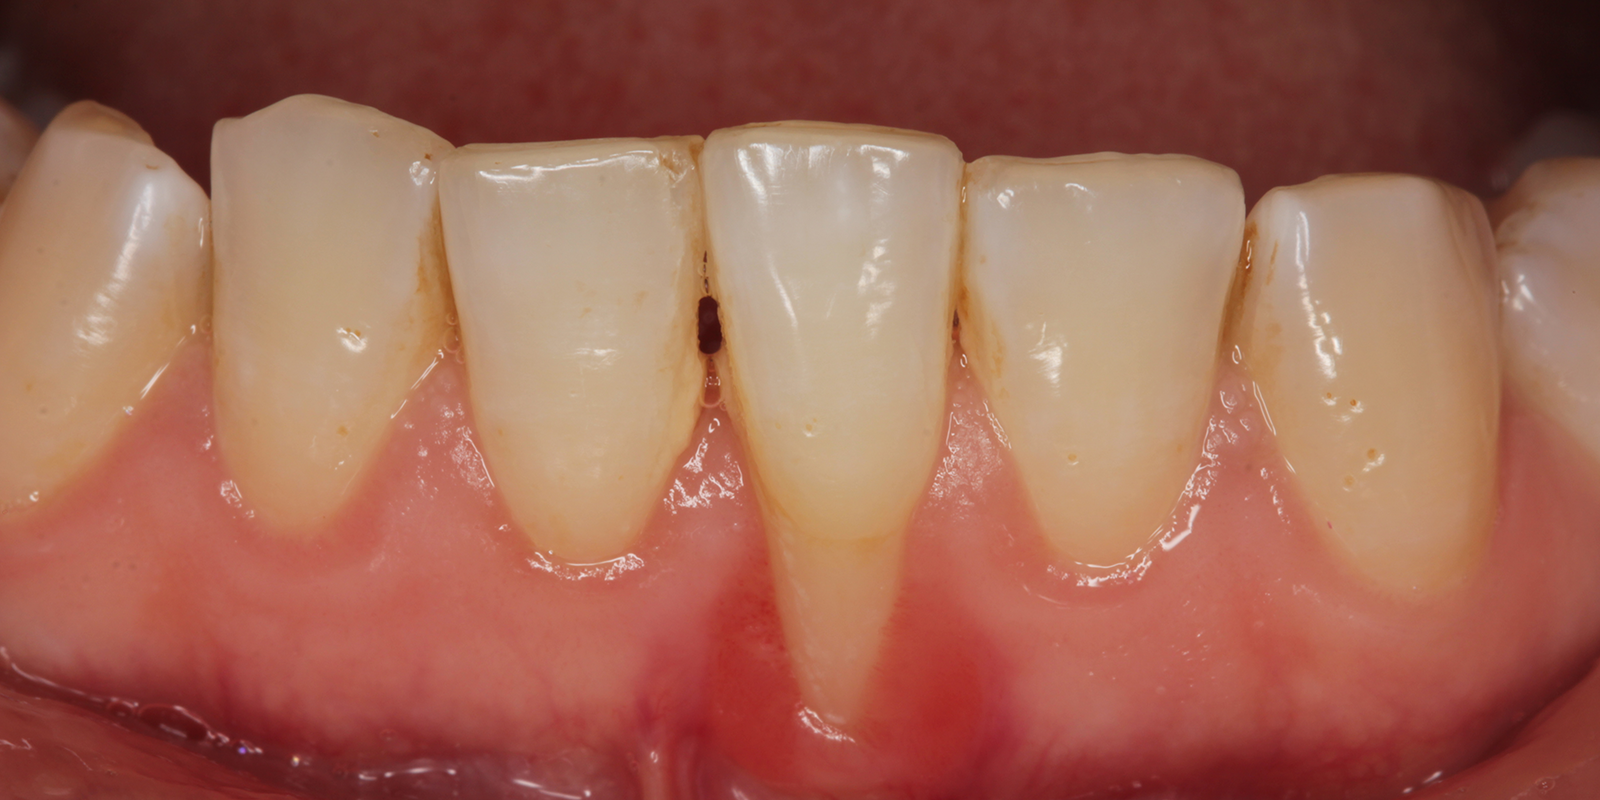

歯周病の始まりは「歯肉炎」です。歯と歯茎の境目に付着したプラーク(歯垢)の中には、1mgあたり約10億個もの細菌が存在します。これらの細菌が産生する毒素によって歯茎に炎症が起こり、赤く腫れたり、出血しやすくなったりします。

この段階では、歯を支える骨はまだ破壊されていません。適切なブラッシングとクリーニングによって、健康な状態に回復させることができます。しかし、歯肉炎を放置すると、炎症が歯茎の奥深くまで進行し、「歯周炎」という状態に移行します。

歯周炎では、歯と歯茎の間に「歯周ポケット」という深い溝が形成されます。健康な状態では、この溝の深さは1〜3mm程度ですが、歯周炎が進行すると4mm以上になり、重度では10mm以上に達することもあります。深いポケットの中は酸素が少ない環境となり、酸素を嫌う「嫌気性細菌」と呼ばれる歯周病菌が増殖しやすくなります。